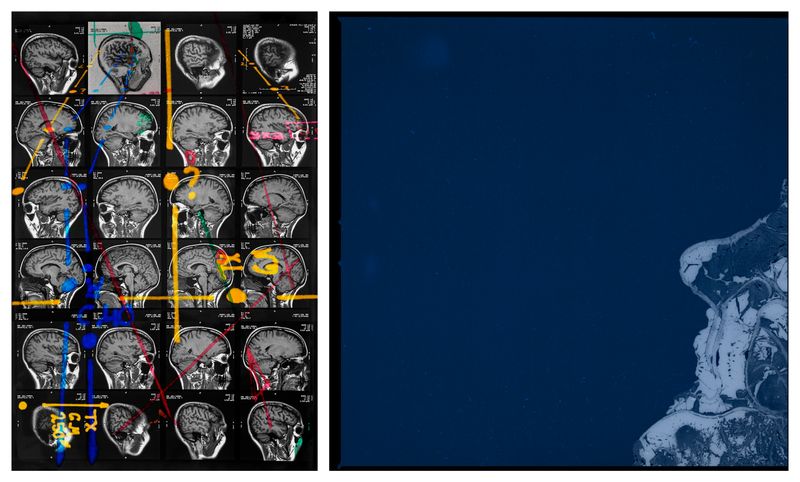

THE PUZZLEThe Life-Long Puzzle.

UNMASKINGThere’s something primal about being diagnosed with AuDHD later in life, it’s as if I have been given permission to deconstruct everything to a cellular level and rebuild it again, purposefully this time, free from the burden of shame and guilt, giving me courage to abandon the constant struggle of masking.

TOPOGRAPHICAL DISORIENTATIONFinding a name for my innate inability to orient myself in my surroundings.

WITHIN REACHI can finally see myself.